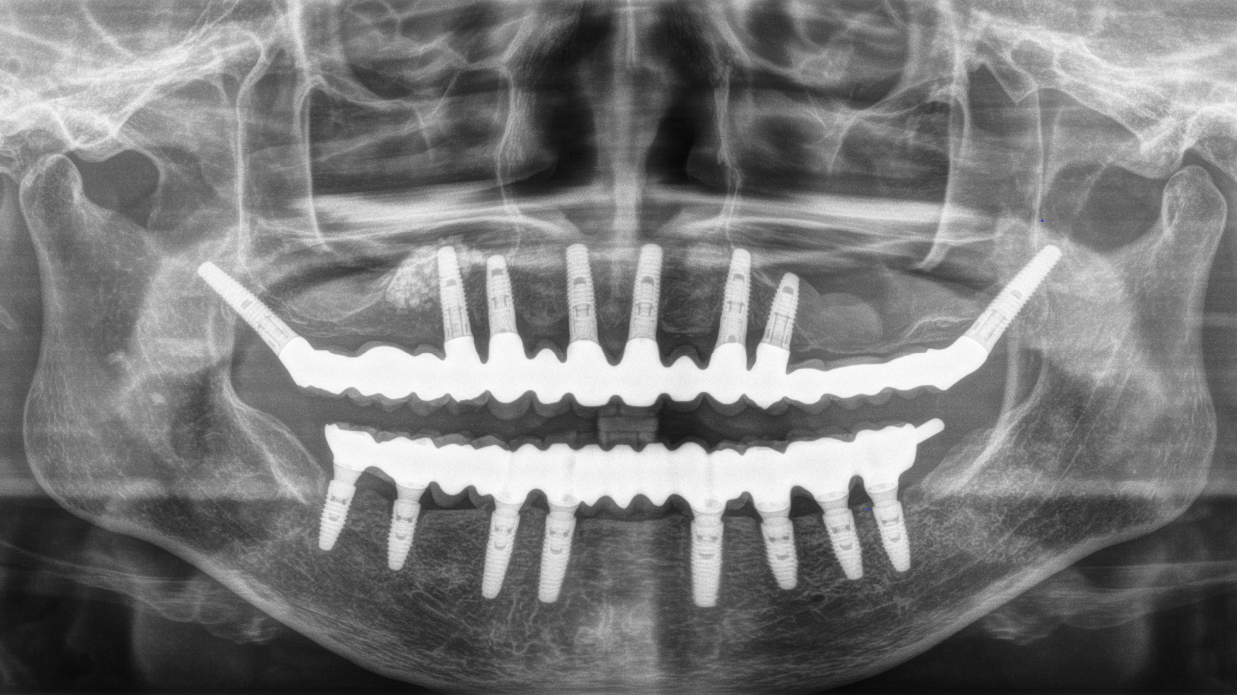

完成後のレントゲン写真

最終的な被せ物を装着した状態のレントゲン写真。

(今回は下顎ですが、その前に上顎は治療済みです。)

【下顎インプラント8本で14本の歯を回復するスクリュー固定タイプ】

インプラント手術:250,000円×8本=2,000,000円

静脈内鎮静法:0円

既製アバットメント:90,000円×8個=720,000円

メタルボンド:130,000円×14本=1,820,000円

マルチアバットメント:25,000円×8個=200,000円

連結料:10,000円×13カ所=130,000円

仮歯:50,000円×8本=400,000円

ポンティック:10,000円×6本=60,000円

ラジオグラフィックガイド(11本):22,000円

埋入ガイド(8本):73,000円

総額:5,425,000円+税